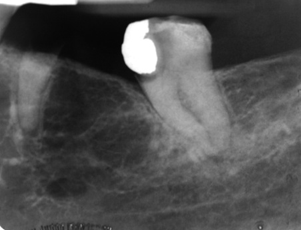

focal osteoporotic marrow defect

likely filled with blood

no epithelial lining

aneurysmal bone cyst